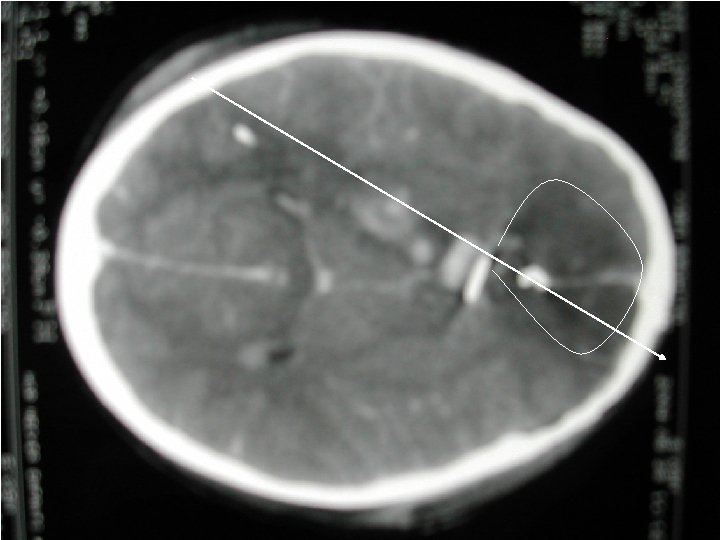

Lésions cranio-encéphaliques • Extrêmement fréquentes: 80% des patients • Hématomes intra-crâniens rares (5%) • Lésions oedèmateuses (60 -80%) • Lésions axonales diffuses les fractures ne préjugent pas de l'importance des lésions Attention: scalp = hypovolémie Traitement = Neuro-réanimation, pas Neuro-chirurgie

Lésions primaires • • • Plaies du scalp, fractures Embarrures, plaies crâniocérébrales Hématomes intracrâniens Lésions axonales diffuses HSD, HED

Hématomes extra-cérébraux • HSD sans lésion secondaire associée • HED avec engagement et œdème diffus

Lésions diffuses

Lésions secondaires • Œdème cérébral diffus • Brain swelling • Ischémie lésionnelle

Œdème diffus et ischémie étendue